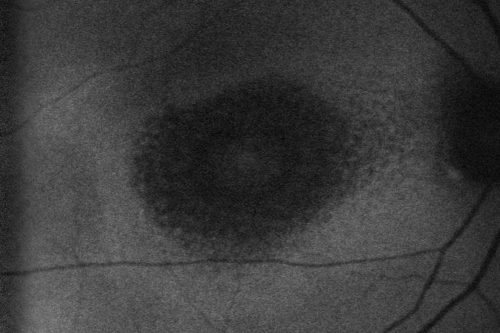

Plaquenil Toxicity - Bull's Eye Maculopathy - 25 Years Therapy - Fundus Autofluorescence

73-year-old woman has been on Plaquenil for twenty five years. Plaquenil has now been stopped for 6 months.  VA continues to decline as does visual function - 20/80 OD , 20/40 OS